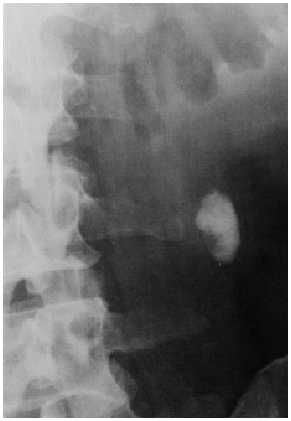

· La urografía excretora, un examen en el cual es necesaria la inyección de contraste en el organismo, es de gran ayuda por que nos da idea tanto de la anatomía como del funcionamiento de la vía urinaria. Nos permite localizar la litiasis y planificar el tipo de tratamiento a seguir.